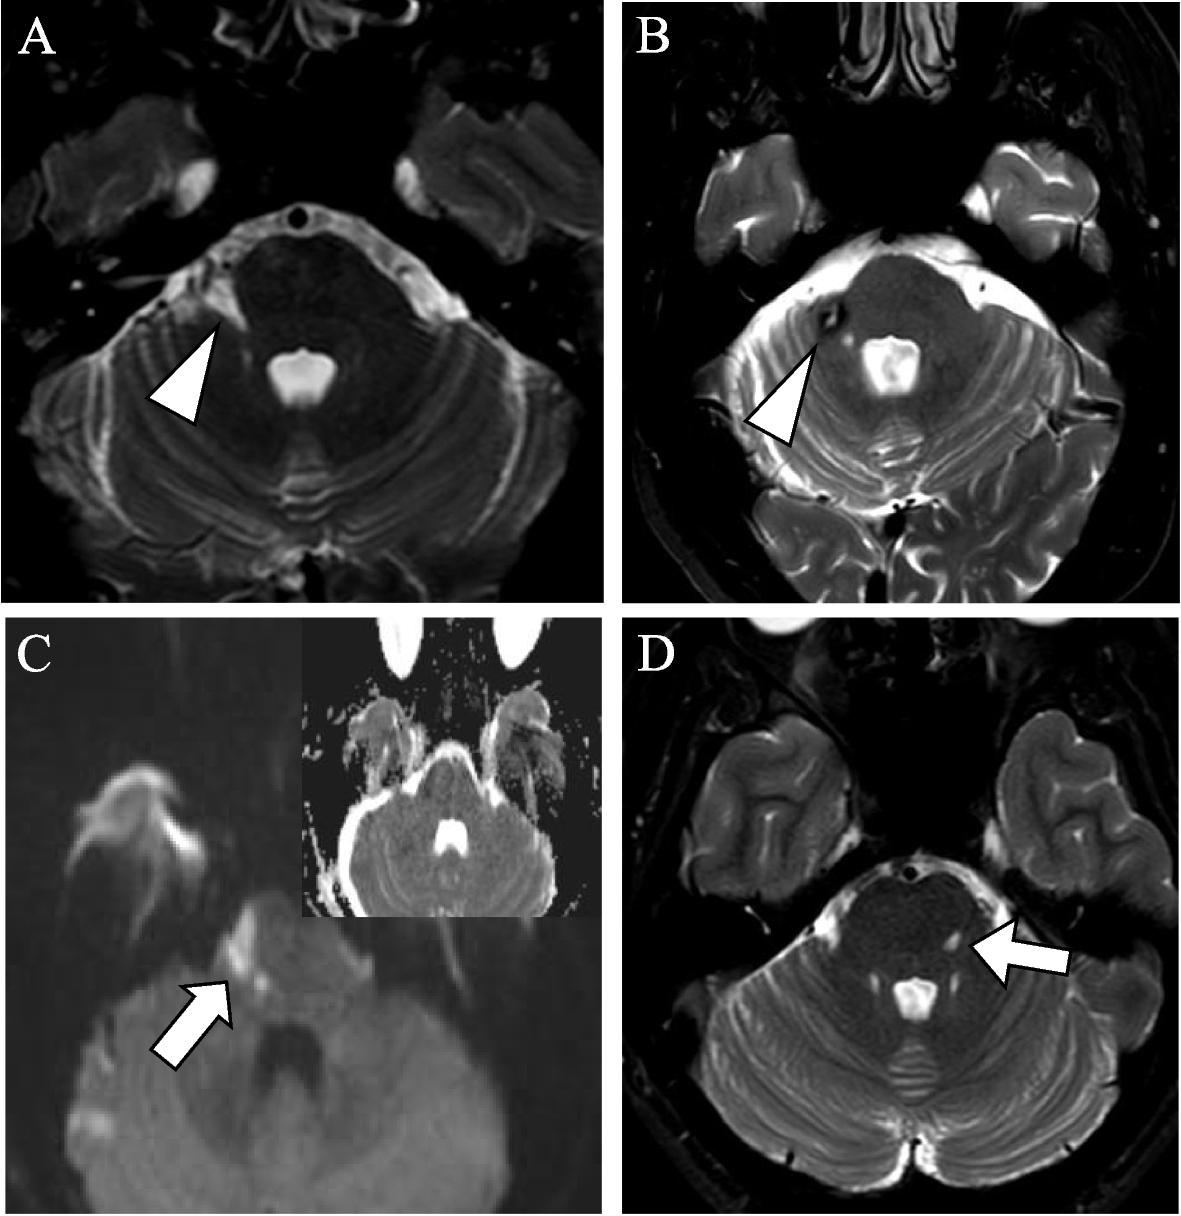

Trigeminal Nucleus Mri